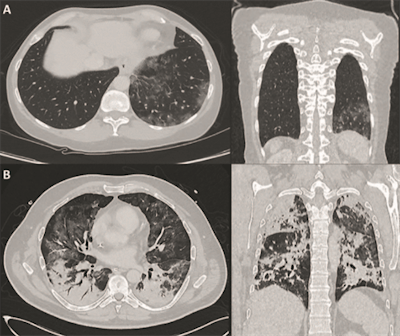

To diagnose and evaluate these conditions, CT is one of the first options, given its ability to detect ground-glass opacities in the lungs. In addition, FDG-PET has long been used to detect and evaluate the severity of inflammation relative to lung diseases, monitor its progression, and determine the efficacy of follow-up treatment.

Lütje and colleagues suggest that FDG-PET/CT be used to monitor response to respiratory therapy and help determine a patient's recovery time. They cited a May 2020 study by Qin et al in which researchers from China found a trend among four COVID-19 patients where greater FDG uptake in SARS-CoV-2-induced pulmonary lesions correlated with longer recuperative times. A maximum standardized uptake value (SUVmax) of 4.6 was observed in one patient who recovered approximately 17 days after the onset of symptoms, while another patient with a SUVmax of 12.2 took more than 26 days after first symptoms to return to health (EJNMMI, May 2020, Vol. 47:5, pp. 1281-1286).

"Taken together, although FDG-PET/CT may not be routinely used in COVID-19 management, especially not in an emergency setting, first data indicate that this imaging modality could play a complementary role in COVID-19 management," Lütje and colleagues concluded. "FDG-PET/CT may reflect changes in FDG-avidity in pulmonary lesions as well as in other organs during the course of COVID-19, potentially clarifying differential diagnosis, estimating the extent of organ involvement and characterizing treatment response during follow-up."